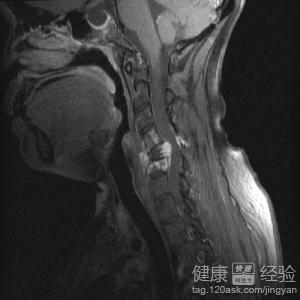

3對於腦血管疾病來說,無論是哪一種,都需盡早診斷。可以結合相關的檢查,如CT/MRI或MRA、DSA及CSF等來發現相應的病灶。還可以結合相關的危險因素,如腦卒中和高齡、高血壓、心髒病、高血脂、吸煙等。